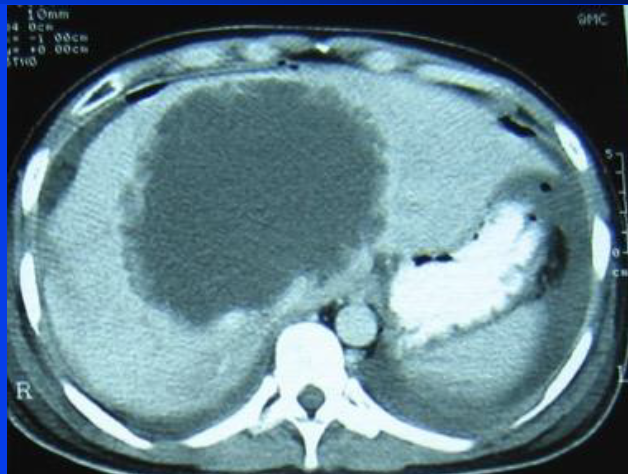

26

Hx: chronic RUQ abdominal pain, sensation of RUQ fullness. Early satiety. Epi: Resident of sheep raising areas worldwide including temperate zones. Exposure to dogs. PE: hepatomegaly Dx? Ix? Rx?

Echinococcus U/S: hypoechoic cystic lesion in the liver CT: septate cystic lesion. Echinococcus Western Blot (+) PAIR / Albendazole / surgery depending on stage